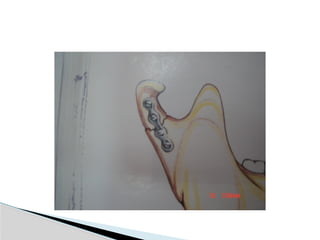

 Mini plates

 Lag screws

 Pin fixation

 Inter osseous wire

Methods of fixation

 Mini plates Lag screws  Pin fixation  Inter osseous wire Methods of fixation